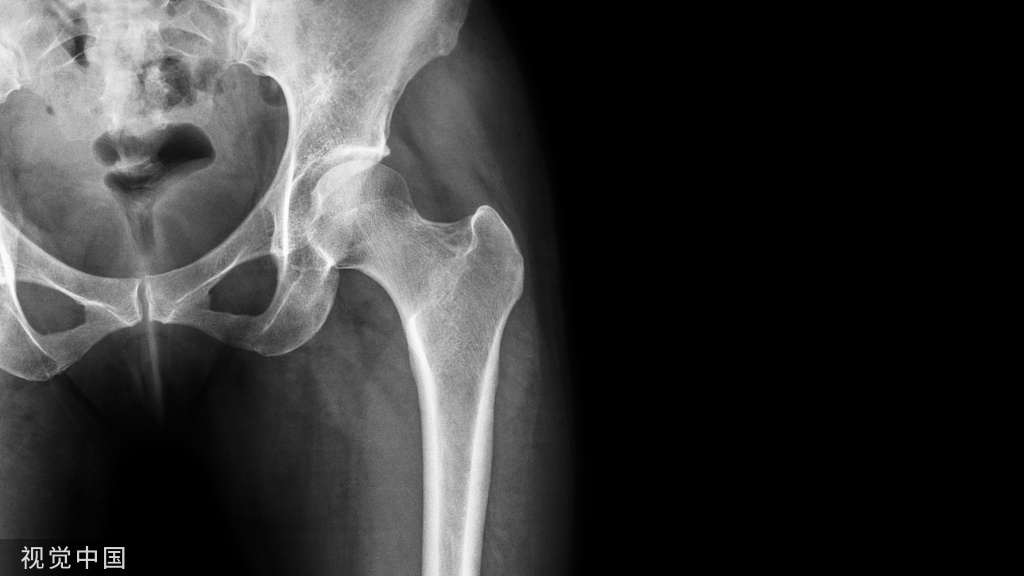

髋部骨折手术